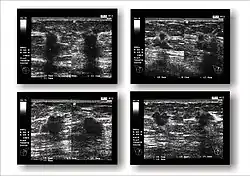

Werden bei der Tast- oder Ultraschalluntersuchung Auffälligkeiten gefunden, folgt als nächste Untersuchung üblicherweise die Mammographie: Die Röntgenaufnahmen werden aus zwei Blickrichtungen (von der Seite und von oben) gemacht, bestimmte Veränderungen erfordern manchmal zusätzliche Aufnahmen. Die Galaktographie wird nur durchgeführt, wenn die Brustwarzen Sekret absondern. Als Ergänzung steht bei einer solchen Sekretion an einigen Zentren die Duktoskopie, eine Spiegelung der Milchgänge, zur Verfügung.

Umgekehrt werden mit der Mammographie entdeckte Veränderungen immer sonographisch weiter untersucht. Dabei werden gutartige Zysten erkannt. Die Kassenärztliche Bundesvereinigung schrieb 2003 hierfür Schallköpfe mit mindestens 5 MHz Frequenz vor.[101] Mittlerweile ist dieser Wert auf 7,5 MHz erhöht worden.[102]

Die Kernspintomographie der Brust (MR-Mammographie, MRT) wird zurzeit nur empfohlen für das invasive lobuläre Mammakarzinom zur Bestimmung der Resektions-Grenzen und allgemein bei Verdacht auf das Vorliegen mehrerer Tumorherde,[103] gegebenenfalls ist auch eine MRT-gesteuerte Biopsie möglich. Nach brusterhaltender Therapie kann die MRT eingesetzt werden, um zwischen narbigen Verdichtungen in der operierten Brust und neuem Tumorwachstum zu unterscheiden. Außerhalb der ambulanten Versorgung der gesetzlich krankenversicherten Patientinnen gibt es weitere Indikationen.

Die Positronen-Emissions-Tomographie ist derzeit keine Routinemethode, kann jedoch eingesetzt werden, um nach dem Primärtumor bzw. dessen Metastasen zu suchen, wenn dieser mit anderen Methoden nicht gefunden werden kann.

Knochenszintigramme, Computertomographien, Röntgenaufnahmen der Lunge, Sonographien der Leber und ggf. Kernspintomographien dienen dazu, nach Metastasen zu suchen, also die Ausbreitung der Erkrankung zu erkennen. Angesichts der Tatsache, dass die PET/CT bis auf die MRT-Hirn- und Brustuntersuchung genauer ist und zugleich auch andere Krebserkrankungen ausschließen kann, erscheint die PET/CT sinnvoller als Knochenszintigramme, Computertomographien, Röntgenaufnahmen der Lunge und Sonographien der Leber zusammen.

Bei der radiologischen Diagnostik kann zudem ein durch Exsudat entstandener Pleuraerguss, wie er beim Mammakarzinom auftreten kann, zuverlässiger als durch Perkussion erkannt werden.[104]